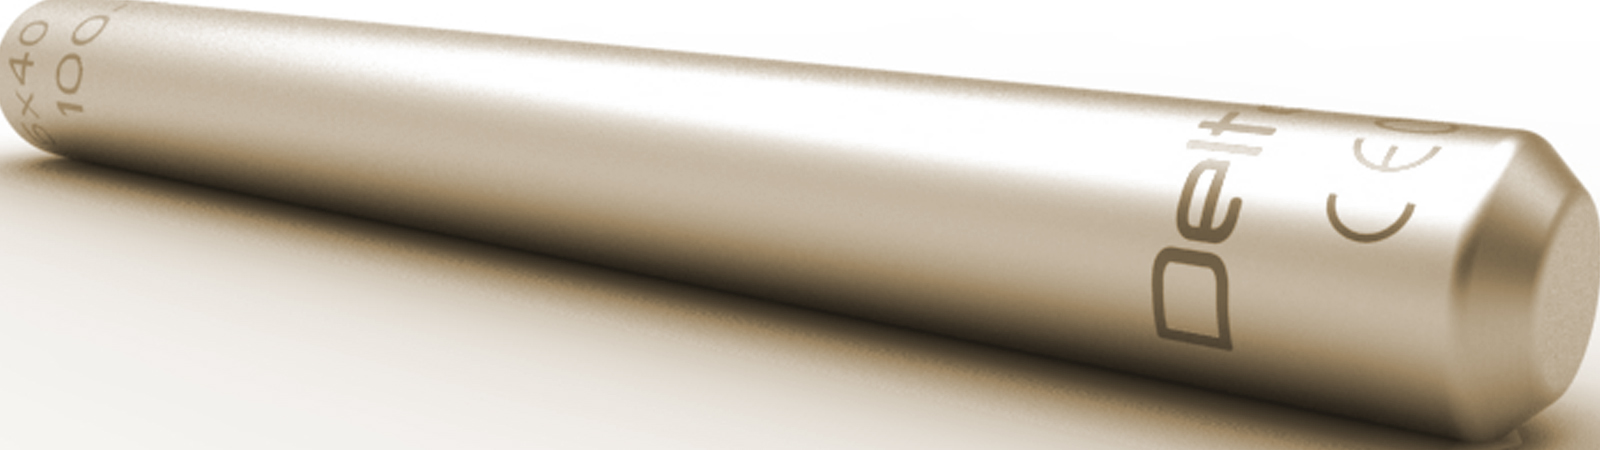

Torpedo bietet eine minimalinvasive Option für die Behandlung von ISG-Dysfunktionen. Das wendelförmige CST-Profil® mit seinem conical-spiral-turn begünstigt einen idealen Pressfit-Kontakt zwischen Implantat und Knochen und erhöht die Fusionskraft in Zugrichtung um ein Vielfaches. Die wendelförmige Profilgeometrie stabilisiert die Bewegungen im ISG Gelenk auch in der Ebene senkrecht zu den Gelenkflächen. Spezielle Oberflächenbehandlungen erzeugen eine definierte und hydrophile Implantatoberfläche.

zurückTORPEDOAugmentation

Torpedo erlaubt bei Frakturen des Saktrums durch seine Fenesteriung im conical-spiral-turn eine feste Verankerung des Implantates mittels Zementinjektion. Der Zement wird durch eine steuerbare Applikationshülse durch die Kanülierung des Implantates eingebracht. Dabei kann jede Austrittsöffnung gezielt angesteuert werden und somit dezidiert in die entsprechenden Voids injiziert werden.